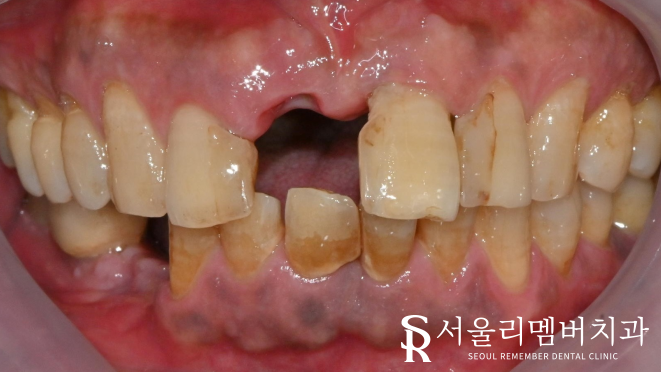

넘어지는 동시에 앞니에 충격이 가해져

이가 부러졌다며 내원하셨습니다.

서울대입구역치과 에서 살펴본 결과,

파절 부위가 적지 않았으며

라미네이트는 적합하지 않다는 판단이 들었는데요.

환자분은 파절 부위가 크지만

신경이 드러나 있지 않았고 감각도 있었는데요.

서울대입구역치과과 에서 엑스레이를 찍어서 확인한 결과

다행히 뿌리에 금이 발견되지 않아

바로 브릿지를 진행해도 되겠다는 판단이 들어

환자분 동의하에 진행하게 되었습니다^^